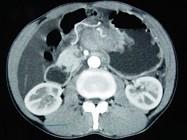

问题 男,65岁,中上腹痛腹胀、消瘦、乏力、纳差,影像检查如图,最可能的诊断是()

选项 A.胃间质瘤 B.萎缩性胃炎 C.肥厚性胃炎 D.胃窦癌 E.胃淋巴瘤

答案 D